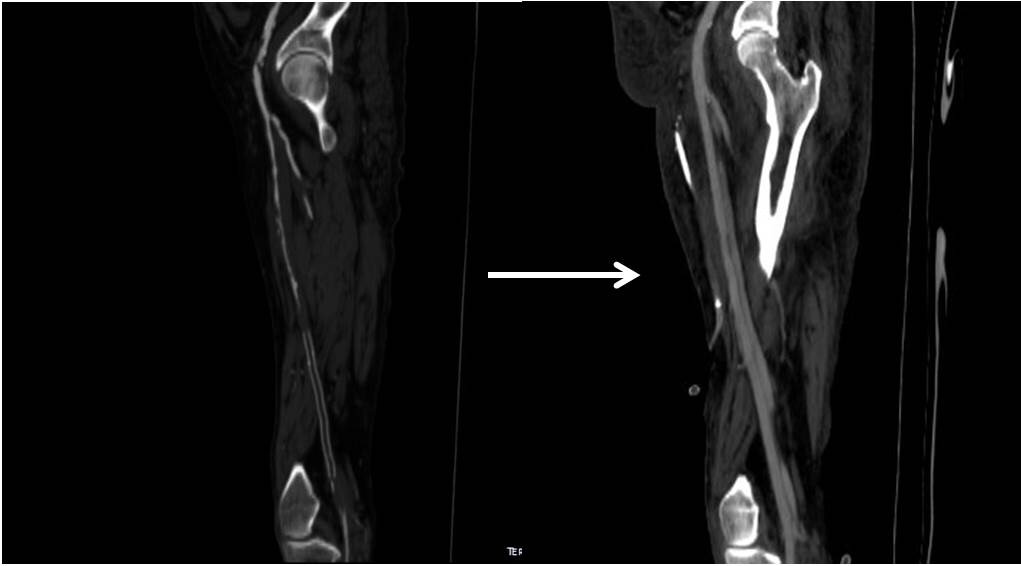

This patient is a younger middle aged man who in his youth experienced a posterior dislocation of his left knee, resulting in an arterial transection. This was repaired with an in-situ graft. Subsequently, he had complications of osteomyelitis and had his knee fused after resection of his joint. He did well with this bypass for several decades, but it finally failed several years ago, and a new one was created (image above).

Rather than directing the graft in line as in the previous one, this was was taken from a medial exposure of the femoral artery and tunneled superficially around the fused knee to coil lateral, ending in the anterior tibial artery.